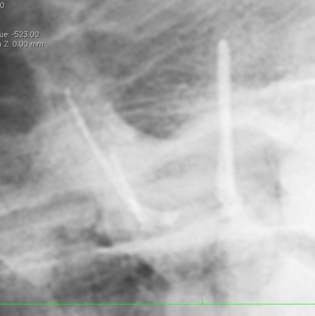

まずは残存ファイルのある根管を見ていきましょう。

画像の丸で囲ってある部分に破折したファイルが認められます。

かなり削りましたが、この状態で初めて破折ファイルを目視することが可能となります。レントゲンではわかりやすいのですが、およそ0.5~0.8mmを見ることが可能です。

少しづつ超音波などで周辺を掘削しファイルを動揺させます。

無事に摘出し新たなファイルを入れた状態です。

それでは今回入れたファイルと以前ファイルを入れられた状態の角度を比較するために画像を重ねて表示してみましょう。

正しくファイルを入れた方向と最初にファイルを破折させた角度を見ると、折れたファイルはかなじ前方から根管口に入っていることがわかります。このような現象は、最初に根管へアクセスする際、歯をあまり削らずに行おうとしたために、急角度にファイルが曲がって根管口へ突入したために破折したことがわかります。下記に示すように、青でファイルを挿入すると折れますが、黄色の位置から挿入すると折れることはありません。根管に対してできる限りまっすぐにいれることのできるアクセスを行うことが重要です。

この症例のガッタパーチャ挿入後の写真です( レジン処置前 )

確実な根管充填ができています。